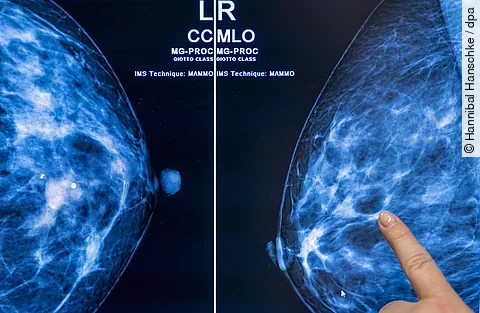

Eine Radiologin sitzt vor mehreren Monitoren in einem Krankenhaus und betrachtet Mammografie‑Aufnahmen.

Mammakarzinom: Risikobasiertes Screening oder jährliches Screening?

Anders als beim herkömmlichen Brustkrebsscreening berücksichtigt das risikobasierte Brustkrebsscreening das individuelle Risiko der jeweiligen Patientin. Es findet in angepassten Intervallen statt und bereits seit einiger Zeit wird die Frage diskutiert, ob es eine Alternative zum jährlichen Screening sein kann. Genau diese Frage stand jetzt im…